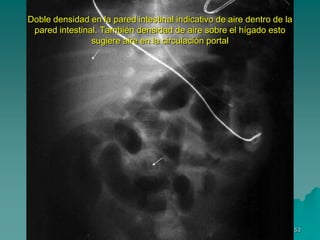

Este documento describe la enterocolitis necrotizante (ECN), una enfermedad grave que afecta principalmente a bebés prematuros. Define la ECN como una lesión intestinal grave causada por una combinación de daños vasculares, de la mucosa y tóxicos en el intestino relativamente inmaduro. Explica los factores de riesgo como la prematuridad, hipoxia, alimentación enteral, infección y mediadores de la inflamación. También cubre el cuadro clínico, diagnóstico, factores pronósticos